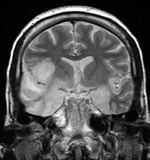

Herpesviral encephalitis A herpetic infection of the brain that is thought to be caused by the retrograde transmission of virus from a peripheral site on the face following HSV-1 reactivation, along the trigeminal nerve axon, to the brain. HSV is the most common cause of viral encephalitis. When infecting the brain, the virus shows a preference for the temporal lobe.[2].

Hsv encephalitis.jpg